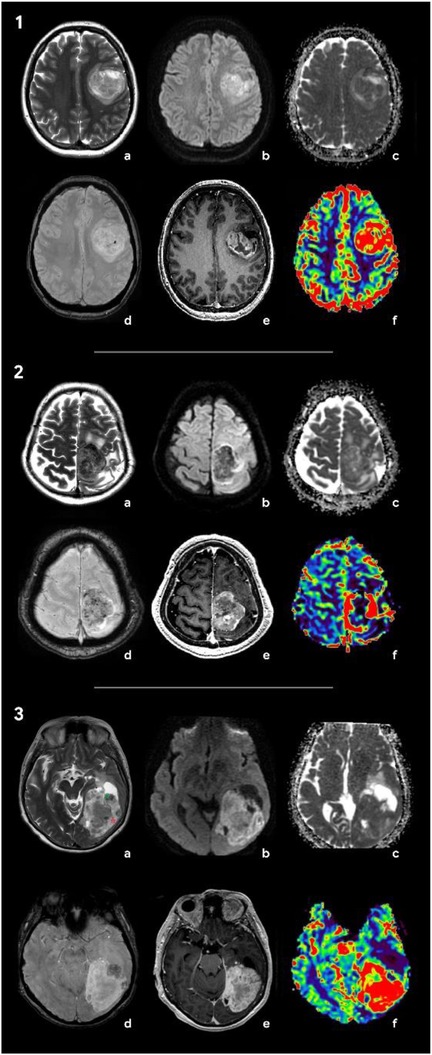

During the preoperative stage, the differential diagnosis included solitary metastasis and high-grade diffuse glioma. There also were suggestions to include in the differential diagnosis anaplastic meningioma. Classic glioblastoma manifestations (Figure 3-1) typically exhibit a ring-like contrast enhancement pattern of the intra-axial solid mass, often accompanied by a central necrotic area. The mass is surrounded by vasogenic edema, in combination with an infiltrative tumor component, which shows no enhancement. Glioblastoma demonstrates a significant mass effect (11). The solid tumor component has restricted diffusion with ADC values measured at 740 ± 200 × 10⁻6 mm2/s (12). Magnetic susceptibility-weighted imaging reveals signal voids attributable to hemorrhages and vascular shunts. Perfusion studies indicate elevated cerebral blood volume (CBV) levels within both the tumor and the perifocal non-enhancing regions, exceeding unaffected white matter values by over fivefold (11, 13). Notably, conventional T2WI findings, frequently overlooked, could provide critical diagnostic insights. Glioblastomas typically exhibit hyperintense signal intensity on T2-weighted images, reflecting their glial architecture (14). This feature complements advanced imaging modalities in distinguishing glioblastoma from other intracranial pathologies.

Figure 3. Radiologic features of the tumors included in differential diagnosis: glioblastoma (1), solitary metastasis (2), and anaplastic meningioma (3). (1) Brain MRI of a patient with glioblastoma: (a) Т2, (b) DWI, (c) ADC, (d) SWAN, (e) T1 + C, and (f) CBV. In the left frontal area, there is a large axial mass involving the cerebral cortex and white matter. The mass shows a ring-like contrast enhancement and contains necrotic areas. On SWAN, the vascular network and single foci of signal void are marked due to the presence of hemoglobin degradation products. On DWI and ADC maps, diffusion is restricted in the solid tumor component. The CBV map shows an increase in tumor blood flow. Т2 demonstrates a hyperintense signal of the tumor. (2) Brain MRI of a patient with brain metastasis of the lung carcinoma: (a) Т2, (b) DWI, (c) ADC, (d) SWAN, (e) T1 + C, and (f) CBV. There is an axial mass located in the left parasagittal region of the junction between the frontal and the parietal lobes. The mass shows a hypointense signal on T2WI and demonstrates vivid contrast enhancement. SWAN detects multiple artifacts caused by microhemorrhages. On DWI, there is a diffusion restriction alongside the tumor periphery. The CBV map shows a threefold increase in tumor blood volume relative to the white matter of the contralateral hemisphere. (3) Brain MRI of a patient with anaplastic meningioma: (a) Т2, (b) DWI, (c) ADC, (d) SWAN, (e) T1 + C, and (f) CBV. In the left occipital lobe, an axial mass with a wide dural base is identified. The tumor has a heterogeneous signal on T2WI with hypointense (green star) and hyperintense (red star) components. The tumor shows an intense and homogeneous enhancement and high blood volume values. SWAN depicts no magnetic susceptibility artifacts.

Intracerebral metastases (Figure 3-2) are typically characterized by heterogeneous T2-weighted signal intensity, a feature attributable to their variable primary origins and the frequent incidence of hemorrhagic transformation (15). The contrast enhancement pattern varies according to the primary tumor type, with some lesions demonstrating necrotic regions. On DWI, the solid component displays restricted diffusion, with ADC values averaging 867.67 ± 138.6 × 10⁻6 mm2/s (13). Peritumoral edema is usually non-infiltrative, which can be confirmed by proton magnetic resonance spectroscopy (1H-MRS), but is histologically definitive. In addition, metastases lack significant neovascularization, resulting in reduced perfusion parameters (in comparison with glioblastomas and meningiomas) both within the lesion and at the periphery of the enhancing margin (15, 16). Meningiomas typically present with conventional imaging features that facilitate definitive diagnosis during differential evaluation. Most cases demonstrate characteristic dural attachment, although atypical localizations may occur, including intraventricular, epidural, or extracranial sites (16, 17). While the majority exhibit benign histology, atypical and anaplastic variants exist and play both clinical and technical roles; that is, they often mimic aggressive central nervous system malignancies (clinical) and also mimic such malignancies in imaging and histopathological appearances (technical) (16, 17). Malignant transformation in these tumors may manifest carcinomatous, sarcomatous, or melanomatous morphological patterns, with cellular features potentially including rhabdoid or clear cell differentiation (16, 17). Imaging may reveal necrotic areas, cystic degeneration, and hemorrhagic foci. Anaplastic meningiomas generally demonstrate intense homogeneous contrast enhancement, reflecting their hypervascular nature and well-developed vascular network (17, 18). Notably, meningiomas and gliosarcomas share overlapping heterogeneous MR signal characteristics on T2WI, which is attributable to their histopathological composition containing both epithelial-derived (hyperintense) and mesenchymal (hypointense) tissue components (17, 18) (Figure 3-3). This imaging similarity necessitates careful correlation with clinical and histopathological data for accurate differentiation.